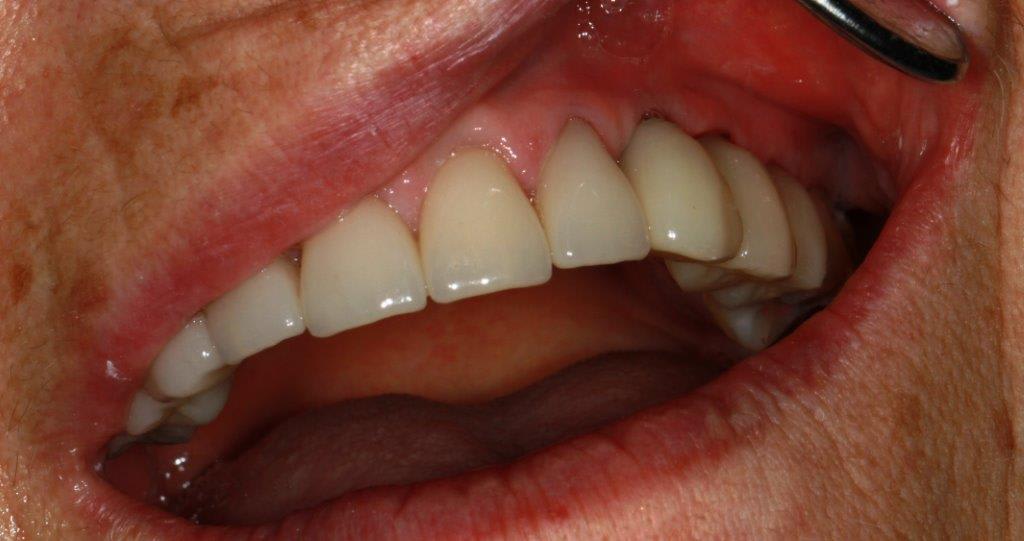

des nouvelles de ce cas... mise en charge des implants et attelle incisive mandibulaires avec suppression du diastème

expansion qui donne un résultat correcte je crois

la temporisation ce fut avec sont stellitte (retouché) puis des provisoires résine, je n'ai pas voulu faire l'empreint des ceram du haut en même temps que les implants.